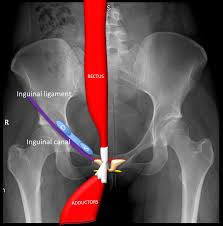

Inguinal Ligament : Inguinal Ligament Muscular System : The ligament also helps to supports the iliopsoas muscles which includes the psoas major muscle that runs from your upper femur, through your pelvis, to your lower spine.. The inguinal ligament is a vital connective tissue structure in the inguinal, or crotch, part of the human body. The inguinal ligament (or poupart's ligament) is a fibrous band extending from the anterior superior iliac spine to the pubic tubercule. Inguinal ligament — noun : Because of its positioning, the ligament is responsible for helping to support the lower. Inguinal ligament is labeled at bottom right.

It forms the base of the inguinal canal through which an indirect inguinal hernia may develop. Read more below!in this video, we explore the following:1 anatomy of the inguinal ligament and canal2 hesselbach's triangle3 basics of inguinal. Choose from 52 different sets of flashcards about inguinal+ligament on quizlet. It plays an important role in preventing the intestines from projecting out from the groin area, offers support for the external oblique muscle in the abdomen and the soft groin tissues. The inguinal ligament is a linear fibrillar echogenic structure deep to the subcutaneous fat and blends with the deep fascia. Check out the pronunciation, synonyms and grammar. It forms the base of the inguinal canal through which an indirect inguinal hernia may develop. Structures passing behind the inguinal ligament.

Structures passing behind the inguinal ligament. Because of its positioning, the ligament is responsible for helping to support the lower. It is an important anatomical landmark and denotes the transition of the pelvis to the lower limb. Ligamentum inguinale nedir ve ligamentum inguinale ne demek sorularına hızlı cevap veren sözlük sayfası. Ligamentul colles este ligamentul reflex și nu ligamentul inghinal. Its anatomy is very important for operating on hernia patients. Medially we can see where the fibers have folded under to form the floor of the inguinal canal. Oblique extends from anterior superior iliac spine to pubic tubercle from pubic tubercle it is reflected to form lacunar ligament continuous with fascia lata. It is an important anatomical landmark and denotes the transition of the pelvis to the lower limb. Inguinal ligament — noun : Uneori se numește ligament fallopian. Read more below!in this video, we explore the following:1 anatomy of the inguinal ligament and canal2 hesselbach's triangle3 basics of inguinal. Learn the definition of 'inguinal ligament'.

El ligamento inguinal está etiquetado en la parte inferior derecha. Inguinal ligament / poupart's ligament lower border of aponeurosis of ext. The inguinal ligament (also known as poupart's ligament or the fallopian ligament) is a fibrous band extending from the anterior superior iliac spine to the pubic tubercle. Its anatomy is very important for operating on hernia patients. (ligamentum inguinale anlamı, ligamentum inguinale latincesi, latincede ligamentum inguinale, ligamentum inguinale nnd). The inguinal ligament supports the muscles that run inferior to its fibers, including the iliopsoas and pectineus muscles of the hip. Below the fold of groin is where. Among the hypotheses advanced to explain this frequency, the role played by the inguinal ligament was underlined.

Frontolateral view of the right side of the pelvis. The inguinal ligament is a vital connective tissue structure in the inguinal, or crotch, part of the human body. Because of its positioning, the ligament is responsible for helping to support the lower. Estructuras que pasan por detrás del ligamento inguinal. It underpins delicate tissues in the crotch and also the outside stomach angled muscle. Structures passing behind the inguinal ligament. Vista frontal lateral del el punto medio del ligamento inguinal, a medio camino entre la espina ilíaca anterosuperior y el tubérculo púbico, es el punto de referencia del nervio femoral. Poupart's ligament webster's new international english dictionary.